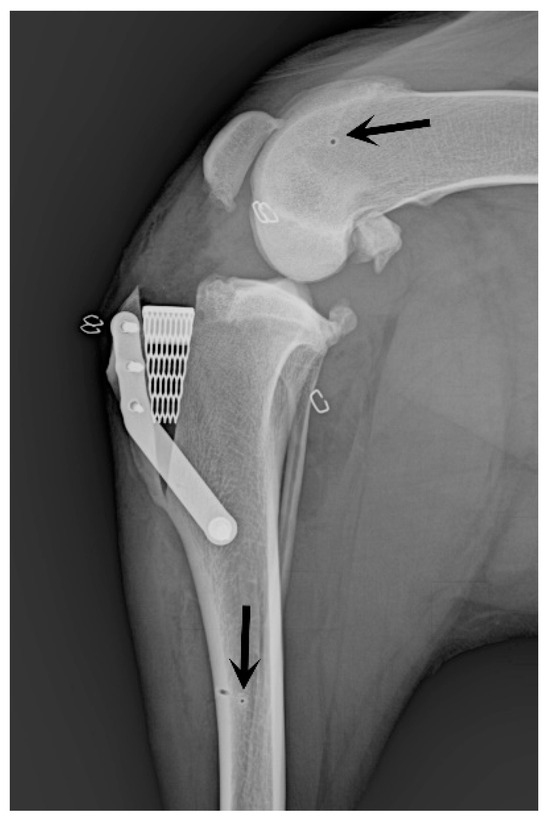

2.4. Surgical Stabilization of the Stifle Joint

2.5. Postoperative Management